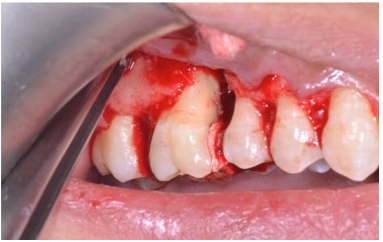

After 4 weeks, surgical intervention was carried out. Under local anesthesia a full thickness mucoperiosteal flap was reflected to entirely expose the underlying bony defect (Figure 3). Scaling and root planing was again carried out with osteoplasty to make sure the site becomes clean and non-infected. Freeze-dried bone allograft (surreoss) 0.5cc powder was condensed into the bone defect (Figure 4) and 1x2cm Acellular Dermal Matrix Membrane (Surederm) was placed over the graft area to prevent the epithelial cell migration (Figure 5). Finally, interrupted silk (4/0) suture were placed to approximate the soft tissue (Figure 6). Post-operative instructions were given and patient was directed to use chlorhexidine gel and rinse three times for a period of 15 days and suitable antibiotics were prescribed for five days. As the prognosis of tooth was highly questionable patient was recalled on follow up after 1 week, 2 weeks and 4 weeks. After 3-months’ patient’s intraoral radiograph showed remarkable improvement in regard to bone repair and patient’s satisfaction (Figure 7). Clinical evaluation on 3-month, 2-year and 5-year recall exhibited marked reduction in pocket depth up to 12mm with radiographic evidence of further hard tissue repair (Figure 8). A 5-year recall showed a stable probing depth of 3 mm with functionally standing in her oral cavity despite the fact that she refused to have a crown on the treated tooth (Figure 9).